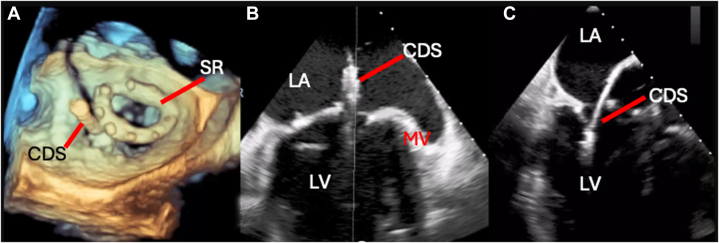

The heart team deemed the patient high surgical risk. TEER was selected, using initial navigation outside the surgical ring. A small clip device was used first to facilitate access, followed by sequential implantation of 2 wide clip devices to optimize MR reduction (Figure 2).

Transcatheter Edge-to-Edge Repair Procedure

The CDS crosses outside of the surgical ring into the LV as seen in the 3-dimensional transesophageal echocardiography reconstruction (A), 2-chamber view (B), and long-axis view (C). CDS = clip delivery system; LA = left atrium; LV = left ventricle; MV = mitral valve; SR = surgical ring.